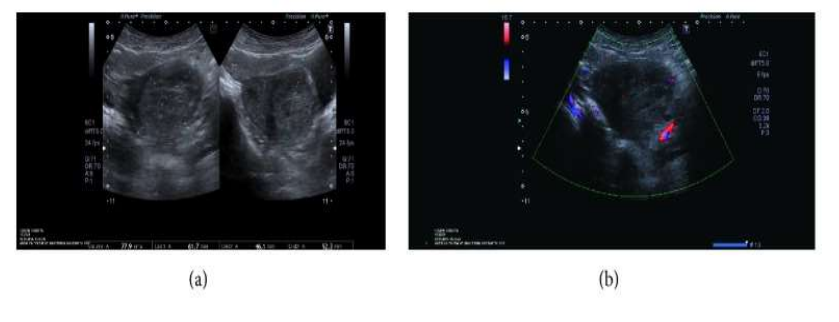

Shintre and Coelho [16] reported a 27-year-old lady who was known to have Thalassemia minor who had manifested with heavy vaginal bleeding and passage of clots over the preceding two days. She stated that she had been having continuous on and off mild to moderate vaginal bleeding pursuant to a second trimester therapeutic abortion she had undergone two months preceding her presentation. She did undergo therapeutic abortion in view of the fact that she had her chorionic venous samples which had shown that the foetus had Thalassemia major due to the fact that both herself and her husband had Thalassemia minor. The therapeutic abortion was induced with utilization of misoprostol (PGE1) tablets. The reports of the obstetrician who undertook the therapeutic abortion did document that the abortion was complete and therefore no curettage was undertaken pursuant to her abortion. She had also undergone another therapeutic abortion 8 months earlier for the same reason following chorionic villous sampling that showed Thalassemia major foetus. This therapeutic abortion was ensued by curettage of her uterine cavity for complete evacuation of her products of conception. She did not have any significant past medical or surgical history. She was noted to be pale or otherwise her general examination was normal. She had speculum examination of her vagina which showed a partially open cervical os that associated with minimal blood clots. There was no active bleeding. Her uterus was bulky, and it measured about 8 weeks to 10 weeks size as well as it was firm to soft in consistency, firm to soft with regard to consistency, mobile and associated with free fornices. The results of some of his laboratory blood tests included: Haemoglobin 9.5 grams per decilitre, platelets 3-lakhs, Serum Beta Human Chorionic Gonadotrophin (B-HCG) 35 MIU/ML which was normal, normal coagulation screen and normal liver function tests. Her blood sample was sent for grouping and saving for future use when required. She had ultrasound scan and magnetic resonance imaging (MRI) of pelvis. The MRI scan demonstrated a bulky uterus that measured 4 cm x 7 cm x 7 cm, heterogeneous lesion within the posterior wall of her uterus, lost endometrial-myometrial interface, multiple dilated tortuous blood vessels within her posterior myometrium which had suggested the likelihood of retained products of conception or gestational trophoblastic tumour which would represent placental site trophoblastic tumour, or uterine vascular malformation (see figure 1). The trans-abdominal ultrasound scan of pelvis did demonstrate an 8.8 cm x 7.5 cm x 7.5 cm bulky uterus the posterior myometrium that was very enlarged as well as heterogeneous with increased vascularity upon Doppler ultrasound scanning (see figure 2). Doppler ultrasound scanning did demonstrate a peak systolic velocity (PSV) of 121 cm / s as well as restrictive index of 0.36. The ultrasound scan also demonstrated that her endometrium was thickened within the lower uterine segment that was suggestive of retained products of conception. She had a chest x-ray which was normal. She had ultrasound scan-guided evacuation of her retained products of conception from her lower uterine segment which was sent for pathology examination. The evacuation of the products of conception did trigger active bleeding. She therefore underwent uterine artery embolization with utilization of cyanoacrylate (glue) (see figure 3). There was no evidence of active bleeding pursuant to her embolization. She was discharged on the 3rd post-procedure op day on oral antibiotics and haematinics. Pathology examination of the tissue did show degenerated and necrosed bits of decidua as well as few degenerate chorionic villi that were admixed with fibrin and blood. The degenerate products of conception did not show pathology examination features of placental site tumour trophoblastic. At her 6-weeks follow-up assessment she stated that her vaginal bleeding had diminished gradually over a period of 4 weeks and the bleeding stopped completely after 4 weeks. She had ultrasound scan of her pelvis with Doppler scan which did show diminished size of the arteriovenous fistula and with diminished vascularity (see figure 4). Shintre et al. [16] stated that the first case of AVM of the uterus was reported in 1926. [17]

Figure 4: After 6 weeks of uterine AVM embolization, USG-pelvis revealed diminished size of AVM (1.3cm x 1.7 cm x 1,5 cm) with diminished vascularity on Doppler. Reproduced from: [16] Shintre H S, Coelho K S. Managing Uterine Arteriovenous Malformation (AVM) Is Like Dealing With Raging Wildfire Awaiting A Spark: Better Be Extremely Cautious & Be Ready With Counter Measures Like Uterine Artery Embolization (UAE). Obstet. Gynecol. Int. J. 2017; 6(1): 00195 DOI: 10.15406/ogij:2017.06.00195

https://medcraveonline.com/OGIJ/managing-uterine-arteriovenous-malformation-avm-is-like-dealing-with-raging-wildfire-awaiting-a-spark-better-be-extremely-cautious-amp-be-ready-with-countermeasures-like-uterine-artery-embolization-uae.html under copy right ©2017 Shintre, et al. This is an open access article distributed under the terms of the, which permits unrestricted use, distribution, and build upon your work non-commercially